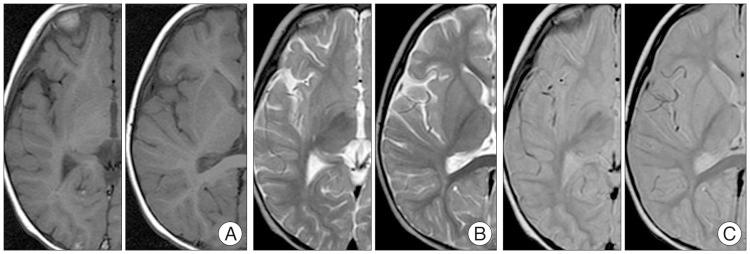

Chronic encapsulated intracerebral hematoma (CEIH) is a rare cerebrovascular disease that behaves as a slowly expanding lesion with a gradual onset. It is well established that CEIH is associated with arteriovenous malformations; however, CEIH associated with cavernous malformation (CM) is extremely rare. We herein report a case of CEIH associated with CM, and discuss its pathogenesis. A 12-year-old female was admitted to our hospital because of a one week history of progressive headache and nausea. Brain computed tomography scan and magnetic resonance imaging showed an intracerebral hematoma surrounded by edema in the right frontal lobe. One week later, her headache and nausea worsened, and a brain computed tomography scan revealed the enlargement of hematoma. A right frontal craniotomy was performed. The capsule, mass, and hematoma were totally removed. Histological examination confirmed the diagnosis of CEIH associated with CM. Immunohistochemical analysis revealed increased expression of vascular endothelial growth factor (VEGF) and the VEGF receptor-1 in the endothelium and fibroblasts. Our findings suggest that the activated VEGF pathway might have positively contributed to development of CEIH in the present patient.

慢性包裹性脑内血肿(CEIH)是一种罕见的脑血管疾病,表现为起病隐匿、缓慢扩大的病灶。目前已明确CEIH与动静脉畸形有关;然而,与海绵状畸形(CM)相关的CEIH极为罕见。我们在此报告一例与CM相关的CEIH病例,并讨论其发病机制。一名12岁女性因进行性头痛和恶心一周入院。脑部计算机断层扫描和磁共振成像显示右额叶有一个被水肿包围的脑内血肿。一周后,她的头痛和恶心加重,脑部计算机断层扫描显示血肿增大。遂行右额开颅手术。完整切除包膜、肿块和血肿。组织学检查确诊为与CM相关的CEIH。免疫组织化学分析显示血管内皮生长因子(VEGF)及其受体-1在内皮细胞和成纤维细胞中的表达增加。我们的研究结果表明,激活的VEGF途径可能对本患者CEIH的发展起到了积极作用。